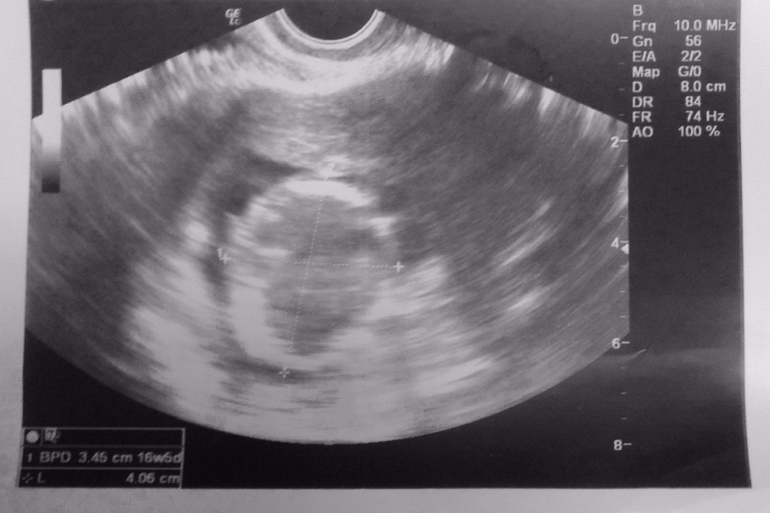

А вот и наш первый скрининг ;)

Пишу отчет с нашего первого в жизни скрининга.

Настроение было отличное, несмотря на не оч хорошее самочувствие вчера, ведь мне предстояла встреча с моим головастиком (теперь я понимаю почему девочки так называют малышей). Голову я увидела оооочень четко на УЗИ!

Сам скрининг состоит их 2-х этапов. 1. УЗИ-скрининг 2. забор крови

Что нам рассказала наш доктор:

Копчико-теменной размер (КТР) плода - 55мм. Доктор мне потом на себе показывала откуда мереет, т.к. я сразу не поняла...

Толщина воротниковой зоны - 1,7мм (важный показатель для исключения синдрома Дауна)

Носовая кость - 3,5мм (так же оч важный показатель, чтобы исключить синдром, при котором ее не видно)

Сердцебиение - 146 ударов в минуту

Затем с результатами узи и фоточками (прикреплю ниже) мы отправились на сдачу крови на ХГЧ и протеин А (РАРР-А) на голодный желудок. Результаты обещали прислать через 2 дня, т.е. послезавтра